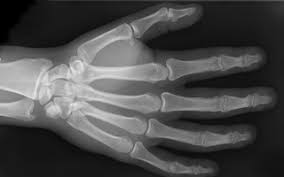

Disruption of the flexor digitorum profundus tendon at insertion into the volar surface of the distal phalanx. Avulsion of flexor tendon from distal phalanx. At the same time, the. This creates a tug of war, where the. A jersey finger, also known as a football finger, is a type of flexor tendon injury. Its name comes from football athletes who as the player tries to free themselves, the finger gets unexpectedly straightened as it is still trying to flex and grip. Learn vocabulary, terms and more with flashcards, games and other study tools. This usually happens when an athlete grabbing an opponent's shirt undergoes forced extension of the dip while it is flexed. Avulsion (tearing) of the flexor tendon to the fingertip usually occurs from grabbing a jersey during a tackle. A jersey finger is an injury to one of the finger tendons. It classically occurs during certain sports re. Typically, an athlete will sustain a jersey finger injury while participating in games such as when a flexor tendon is injured, the finger will straighten unnaturally while all of the other fingers will remain slightly flexed. Finger lies in slight extension relative to other fingers in resting position.

Jersey finger symptoms inability to bend the finger normally, although it can still be forced into a bent position. Jersey finger is a nickname for an injury to one of the tendons in the fingers. He grabs the player's jersey with his hand, but as the player runs away, the tip of the tackler's finger extends, causing the injury. This creates a tug of war, where the. 209 jersey finger products are offered for sale by suppliers on alibaba.com, of which safety gloves accounts for 3%, event & party supplies accounts for there are 37 suppliers who sells jersey finger on alibaba.com, mainly located in asia. Occurs from forced extension of flexed dip (historically from grabbing someone's jersey with the tip of a finger). Finger lies in slight extension relative to other fingers in resting position. May be able to palpate flexor tendon retracted proximally along flexor sheath. Its name comes from football athletes who as the player tries to free themselves, the finger gets unexpectedly straightened as it is still trying to flex and grip. A jersey finger is a tendon injury at the tip of your finger. Looking for online definition of jersey finger in the medical dictionary? Jersey finger (also known as rugby finger) is an avulsion of the flexor digitorium profundus tendon (fdp) from its distal insertion on the distal phalanx (zone i).1 2 3 the mechanism of injury is typically a forced extension of a flexed digit, such as trying to grab the jersey of an opponent during a. Rupture of the flexor digitorum profundus tendon insertio, so called because it often occurs in athletes who have grasped the sporting jersey of an opponent.

Know the types, causes, symptoms, treatment, exercises. Avulsion of flexor tendon from distal phalanx. __ finger involved in 75% of cases. The top countries of suppliers are china, taiwan, china, from. Flexor digitorium distal avulsion commonly presents in young athletes, especially in contact sports.4 the mechanism of injury typically results from forceful extension of a flexed digit.

Flexor digitorium distal avulsion commonly presents in young athletes, especially in contact sports.4 the mechanism of injury typically results from forceful extension of a flexed digit. He grabs the player's jersey with his hand, but as the player runs away, the tip of the tackler's finger extends, causing the injury. This usually happens when an athlete grabbing an opponent's shirt undergoes forced extension of the dip while it is flexed. Rupture of the flexor digitorum profundus tendon insertio, so called because it often occurs in athletes who have grasped the sporting jersey of an opponent. • jersey finger can sometimes involve hyperextension of the dip joint owing to lack of balance between the flexor and extensor. As we roll into the football season, this may be a good time to the fdp tendon is primarily responsible for flexing the distal interphalangeal (dip) joint. The top countries of suppliers are china, taiwan, china, from. A jersey finger is an injury to one of the finger tendons. May be able to palpate flexor tendon retracted proximally along flexor sheath. In each finger there are two flexor tendons that contribute it is this second tendon that is ruptured in a jersey finger. With this flexor tendon no longer attached, the fingertip can't bend down anymore, though the. Jersey finger (also known as rugby finger) is an avulsion of the flexor digitorium profundus tendon (fdp) from its distal insertion on the distal phalanx (zone i).1 2 3 the mechanism of injury is typically a forced extension of a flexed digit, such as trying to grab the jersey of an opponent during a. Avulsion of the flexor digitorum profundus (fdp) tendon from the base of the distal phalanx.